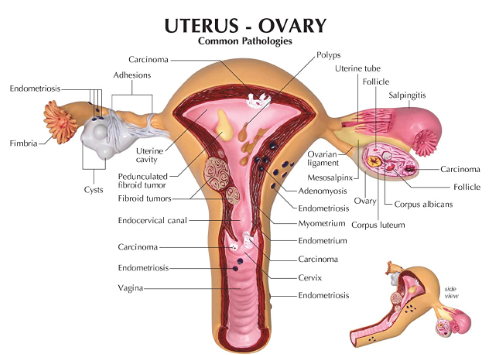

The major gynecological cancers amenable to screening are –

- Cervical cancer

- Uterine cancer

- Ovarian cancer including cancer of the fallopian tube

Uterine Cancer

Uterine Cancer – usually presents with heavy irregular vaginal bleeding. Hence it is usually diagnosed in early stages. But there does exist a pre-cancerous condition which is called Endometrial Hyperplasia. This is the result of excessive growth of the inside lining of the womb and is caused by excessive oestrogen hormone stimulation. The bleeding is usually very heavy during periods and can last unusually long, there can also be bleeding in between periods. That is why, if you have heavy periods your doctor would suggest a hysteroscopy and endometrial biopsy- so that endometrial hyperplasia an be detected and treated before it progresses to malignancy.

Cancer of the ovary and the fallopian tube

Cancer of the ovary and the fallopian tube- this is one of the most dreaded cancers of the female genital organs, and this because it is asymptomatic until a late stage. Often it is difficult to determine whether the cancer originated in the in the tube or ovary due to the close proximity of the two, and because the same histological type of cancers can occur in both.